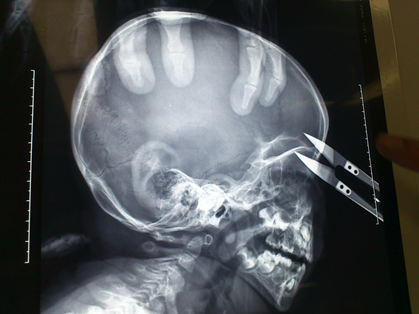

淘气男童“长剪”刺眼 巧手医生“拔刀”救命

两岁八个月的淘气小男孩,在父母照看的空隙,手持10寸长的剪刀玩耍,一不小心深深扎入眼眶,疼坏了宝宝,急坏了父母。8月1日上午,在我院眼科周晓艳和神经外科张祎年两位医生的主刀下,对其实施了眶内异物取出术,使这个淘气宝宝转危为安。

据了解,这个淘气宝宝叫小武,武山县雷口村人,7月31日下午6时许在家玩耍时,趁父母不注意拾起放在炕边上的一把剪刀奔跑嬉戏,不小心被绊了一下,剪刀一下子扎进了小武的左眼眶。家人发现后立即送往当地医院做了简单处理后,随即转往我院。8月1日凌晨12时到达后,多学科会诊后得出结论:由于扎入的剪刀比较脏,且异物在眼眶内存留时间较长,容易导致颅内感染,严重时可引起败血症,伤情十分严重,需立即住入重症监护室并接受手术治疗。8月1日上午9时,实施了眶内异物取出术,历时半个多小时的手术取出了险些要命的剪刀。目前,小武病情稳定,正在康复过程中。